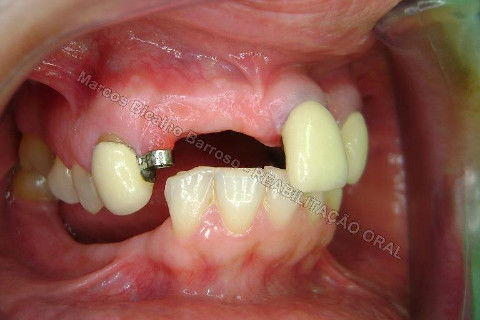

Paciente sexo feminino, 40 anos, queixava-se da situação da PPR superior, sem estabilidade, fraturas constantes nos dentes instalados. Sua vontade era resolver somente o problema da arcada superior, por questões financeiras. Logo no exame clínico inicial verifiquei a necessidade da reabiltiação inferior, pois este caso consistia em desarmonia oclusal severa, principalmente pela extrusão dos elementos 13,14 e 15 devido ausência de várias unidades inferiores. A proposta aceita pela paciente foi a instalação de 5 implantes na mandíbula + 5 implantes na maxila + tratamento endodôntico, osteoplastia e gengivoplastia nos dentes extruídos, incluindo núcleos metálicos e coroas em metalocerâmica (13,14,15). As coroas sobre implantes serão incialmente provisórias em resina fotopolimerizável e posteriormente metalocerâmica, de acordo com as possibilidades da paciente. Os procedimentos nos elementos extruídos serão apresentados em momento oportuno.

Fotos do caso